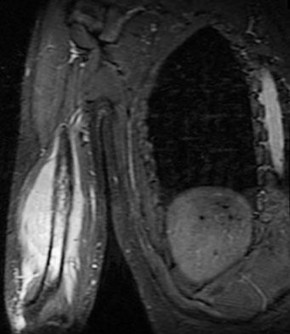

A 15-year-old male presents with deep knee pain awakening him at night. Radiographs show a permeative destructive lesion in the distal femoral metaphysis with a 'sunburst' periosteal reaction and Codman's triangle.

Biopsy confirms high-grade conventional osteosarcoma. What is the most critical prognostic factor for long-term overall survival in this patient?

Explanation

For localized high-grade osteosarcoma, the most important prognostic indicator is the histologic response to neoadjuvant chemotherapy. This is evaluated during the definitive resection. A 'good response' is typically defined as greater than 90% or 99% tumor necrosis. Patients who achieve this level of necrosis have a significantly improved disease-free and overall survival rate compared to 'poor responders' who have extensive viable tumor cells remaining.